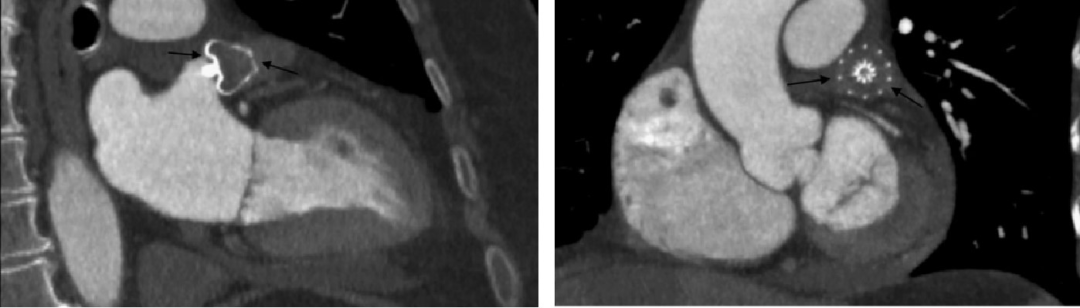

术后:术后45-60天服用口服抗凝药物(华法林或NOAC),45-60天后改为双联抗血小板药维持6个月;如封堵良好,6个月后复查TEE或CT(图2),如封堵良好,改为阿司匹林终身单抗。对于出血高危患者也可以在术后即可进行双联抗血小板,6个月后改为单抗。

图2 CT影像下的LAAO封堵器